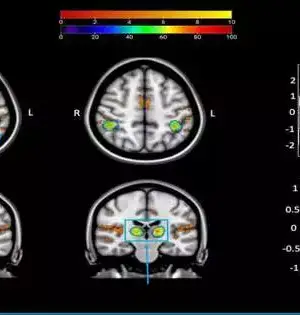

Our recollections are filled with detail: we can vividly recall the color of our house, the layout of our kitchen, or the front of our favorite café. Neuroscientists have long been baffled as to how the brain encodes this information. In a new Dartmouth study, researchers discovered a neural coding process that permits information to be transferred between perceptual and memory regions of the brain. The findings are reported in Nature Neuroscience. Prior to this discovery, the standard theory of brain organization was that perceptual parts of the brain represent the world "as it is," whereas the brain's visual cortex